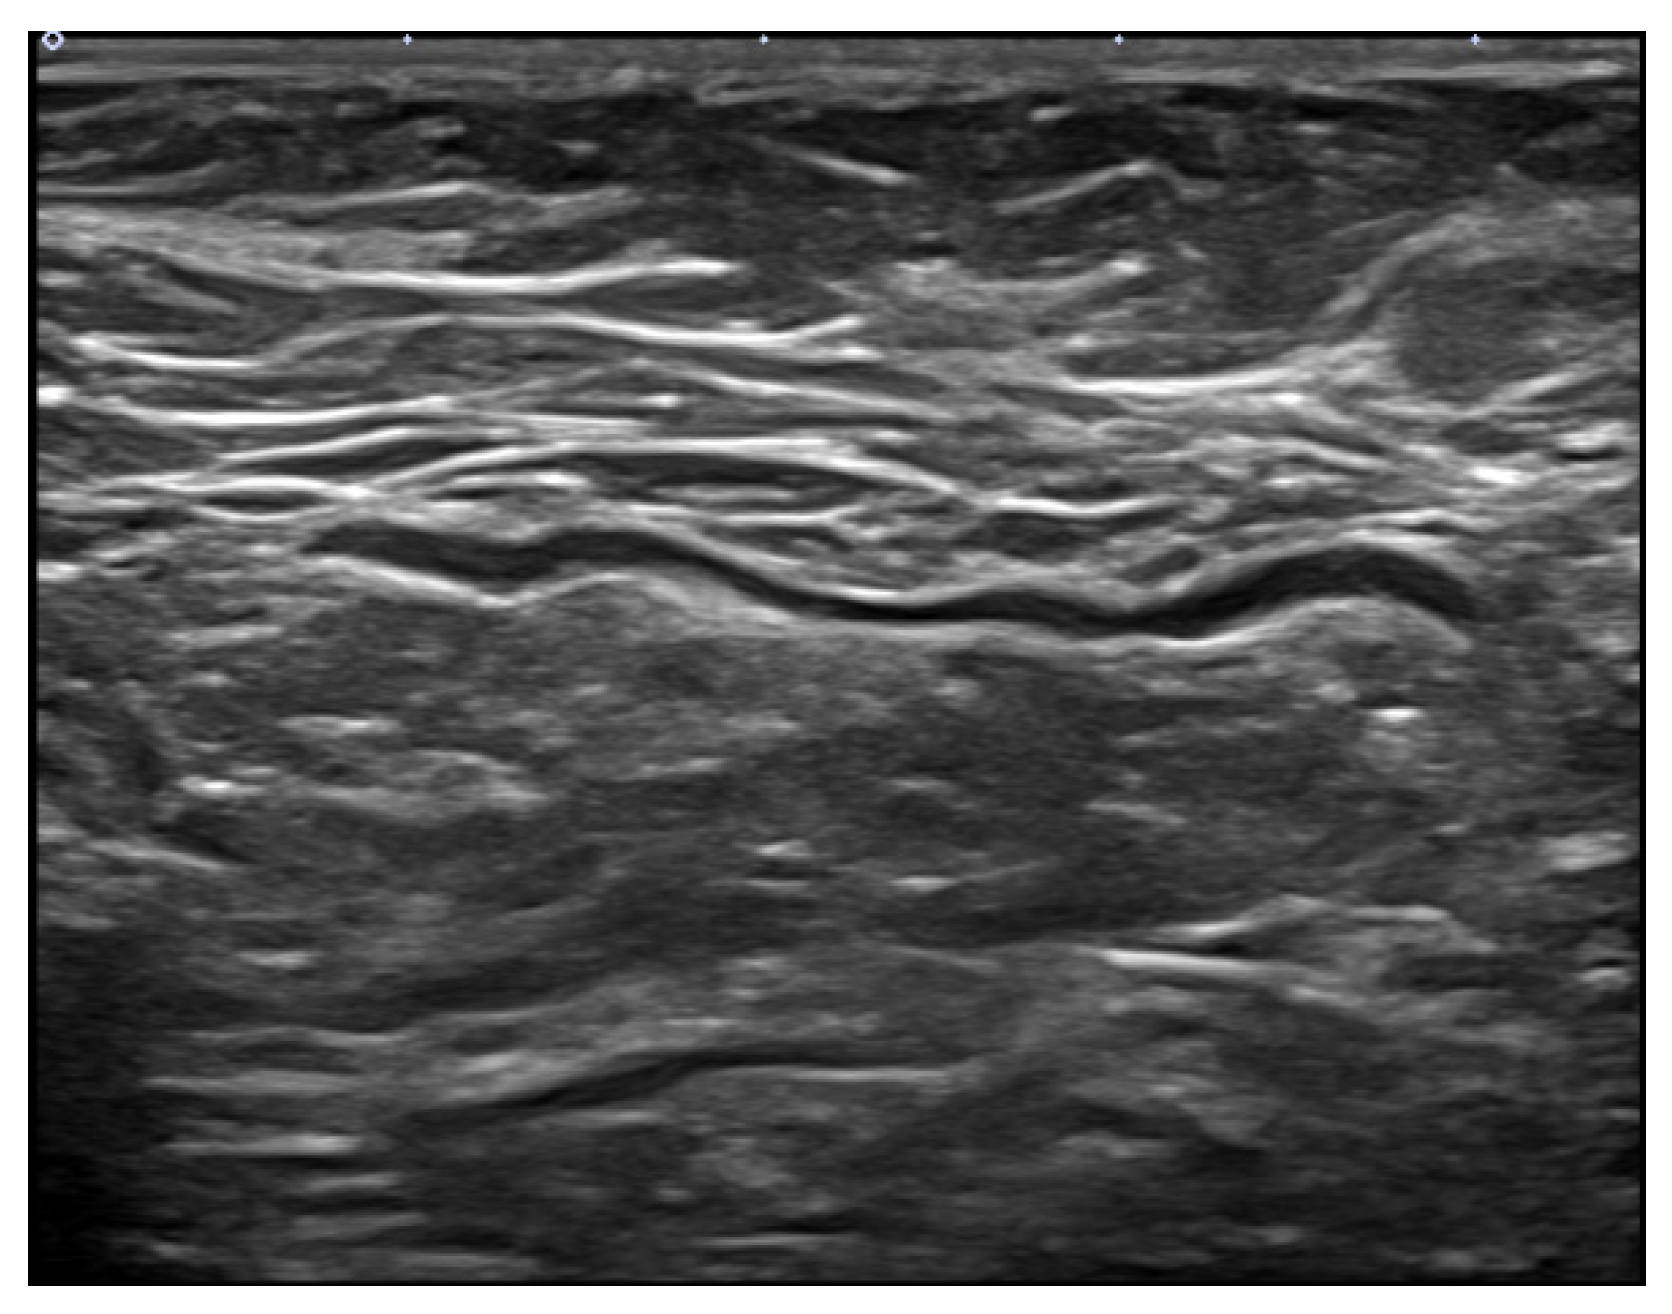

2.2. Ultrasound Technique